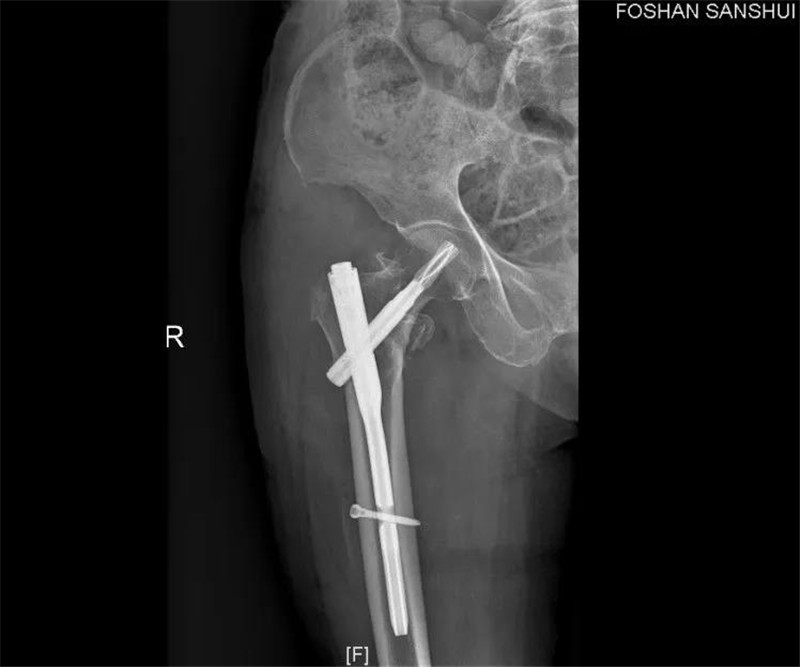

经过4天的内科治疗后,3月9日重新评估病情,老人状态达到手术指标,手术由创伤骨科刘子卿副主任医师主刀完成微创手术,手术切口仅开两道不足3cm的口子,就将约20cm长的钢钉固定在骨折端,半个小时后,手术成功完成。两天后,老人即可下地站立,于23日治愈出院。

两道手术开口都比较小